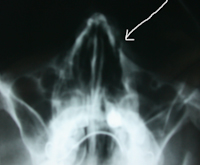

Aspects radiologiques de factures du nez